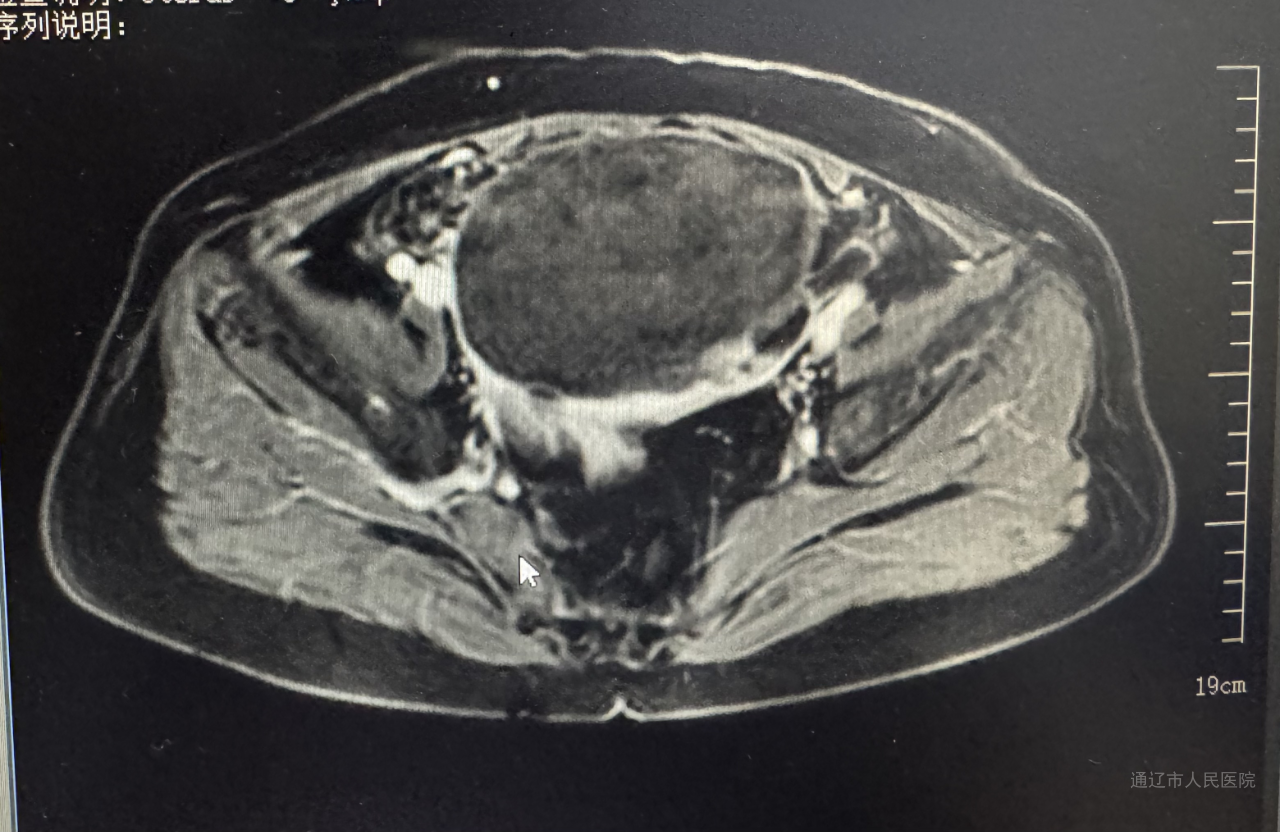

44岁患者左某某痛经10年加重,子宫增大如孕20周(18.3x12.3x17.4cm),经内分泌会诊诊断合并2型糖尿病性酮症、继发贫血及肿瘤标志物CA125>1000。经血管介入科行子宫动脉栓塞止血治疗,后经内分泌科调整血糖后再次转入我科行腹腔镜手术,此次手术依旧由白鹏来主刀,佟金荣、周所霞、程红岩协助,通过旋切器逐步缩小巨大子宫。快速病理结果显示为良性,术后第三天,患者术后第三天恢复良好。